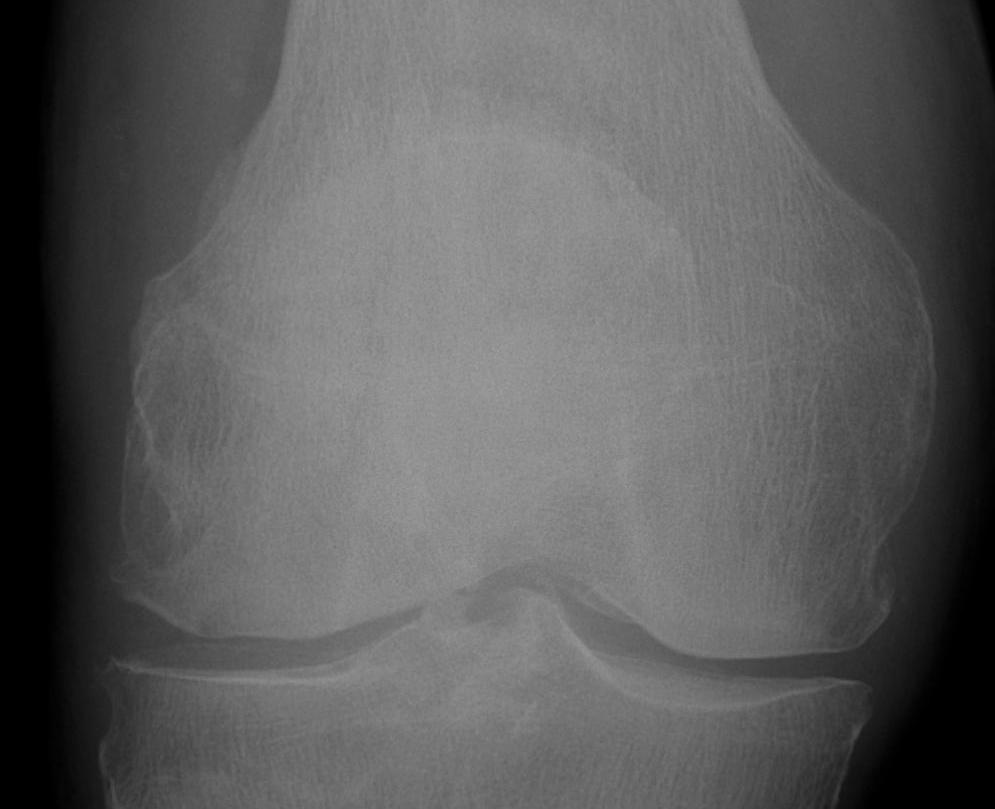

Types

1. Vertical

2. Transverse

3. Burst / Stellate